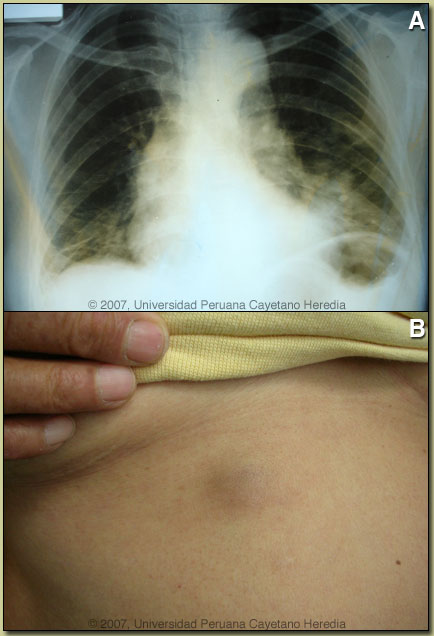

| Diagnosis: Paragonimiasis, Pulmonary and Cutaneous. |

Discussion: After 4 negative tests, the fifth sputum processed and examined for ova and parasites demonstrated eggs of Paragonimus sp. [Image G]. Paragonimus eggs are destroyed in sputum being processed for acid-fast staining so sputum needs to be processed for O&P detection in order to detect eggs. Identical ova were demonstrated in the stools of our patient. Serology is not readily available. Biopsy of the skin lesion [Image H] showed fibroadipose vascularized tissue surrounding a cavity covered by granulation tissue with acute and chronic inflammation and palisading histiocytes with a tendency to form granulomas. There was a moderate eosynophilic infiltrate. Acid fast stain was negative.

On further questioning, the patient related that about 2.5 years ago she was feeling tired, some weakness, back pain, loss of weight, and thought she had cancer. Friends and relatives advised her to eat crabs from the local rivers, a food which she previously consumed infrequently. She began to regularly consume uncooked crab “ceviche” about 1 year before the onset of skin and respiratory symptoms. Paragonimiasis is a zoonoses caused by infection with lung flukes (trematodes) of various species. In Asia, the infection is most prevalent in China, Korea, Japan, Taiwan, and Thailand, with Paragonimus westermani the most common species. Other Asian species infecting humans include P. skrjabini, P. miyazakii, and P heterotremus. Infection in West Africa is due to P. africanus and P. uterobilateralis. In Central and South America infection is due to P. mexicanus though the nomenclature is confusing as authors in several countries have published cases as P. peruvianus and P. ecuadorensis among other names. Rigorous molecular speciation of Paragonimus in Latin America has not been performed. Adult flukes live encapsulated in cystic pockets in the lung parenchyma but may also be found in extrapulmonary locations. Parasite eggs pass into bronchi and are either coughed up into the environment or swallowed and passed in feces. On reaching fresh water they undergo an obligatory passage through a snail intermediate host and after emerging pass into a crustacean, which is a second intermediate host where they mature to infectious metacercaries which can be transmitted to humans eating undercooked crabs. The metacercariae penetrate the duodenum, pass through the diaphragm and travel to the lung parenchyma where they complete maturation. Adult flukes may live for 20 years. Clinically, patients present with cough, sputum, and progressive chest discomfort. The sputum is characteristically tenacious and gelatinous and the hemoptysis generally of a rusty brown color and not bright red. Fever is sometimes present and up to half of patients complain of some dyspnea or wheezing. Eosinophilia is often present. Cysts in the brain are more common in Asia and spinal cord disease may occur. Migratory subcutaneous nodules occur in all species but are most common in P. skrjabini. Radiologically, our patient presented in a typical fashion. With initial ill-defined opacities evolving to multiple cystic lesions. Extensive infiltrative inflammatory lesions, pleural thickening and fluid are also common. The cavities may be multilocular. The scenario presented here is common in that patients in highly TB endemic areas with hemoptysis and infiltrative lung lesions are often misdiagnosed as tuberculosis even though fever and systemic symptoms are uncommon in paragonimiasis. The patient was treated with praziquantel, the treatment of choice, 3 weeks ago and within days her respiratory symptoms and hemoptysis improved. The absolute eosinophil count has decreased to 935 at present.